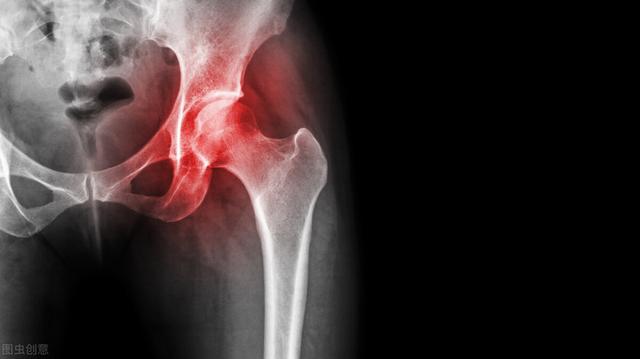

为什么风湿很难治疗?如何治疗类风湿性关节炎最好最有效?

专家指出:风湿性关节炎不是治疗不好,也不是治疗不好,而是治疗针对性不够。很多患者只处理眼前的痛苦,但病情还是每年治疗,每年重复。目前风湿性关节炎没有根治的方法,但患者可以在关节完全融合前立即治疗,达到临床康复的效果(疼痛消失,接触活动有限,病情不再发展)。

细菌性炎症是疼痛和早晨关节僵硬的罪魁祸首。关节粘连是患者受限和举手困难的主要原因。免疫障碍是疾病的根源。传统的血液和电脑断层扫描检查只检查是否有炎症,不知道炎症的详细分布和数量。我不知道免疫障碍的原因。一旦诱发因素,疾病将继续发展。

无菌炎症能刺激滑膜组织水肿、增生,从而产生痛苦、僵直的感觉,专家临床研究表明:无菌炎症可侵入皮下5cm,但传统药物只能渗入皮下2cm,只能祛除关节囊炎症,对深层无菌炎症无能为力。无法消除炎症。这种不舒服的症状会自然地复发。

伴随着风湿症状的发展,病人最明显的感觉就是关节像胶水一样坚硬,抬起手臂,弯腰蹲下,这是由于炎症堆积,滑膜增生厚度,导致软安排粘连,骨质钙化或交融所致。若不能及时了解这些部位的肌肉和韧带解开,若选用药物及注射等治疗方法,只能缓解关节疼痛。

风湿的痛在关节,根在免疫免疫系统的紊乱是风湿性关节炎的发病原因。所以,在临床治疗中,无论哪一个时期的病人,都需要在祛除部分无菌炎症,修正骨质后,对其进行根部治疗。这就是说,吸附在病人血液中的免疫赞同物和炎症因子等,使异常亢进/低下的免疫恢复平衡,阻止炎症再生。回首病人的治疗史,大多数病人关心的不只是症状是否被解除,很多时候会忽视全身免疫平衡的重要性,这就是病人每年治疗,每年复发的根源。